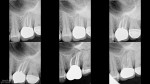

In today post recent symptoms on this tooth I retreated in 2010.

Short-term followups from 2010, 2011, 2012 and then broken today.